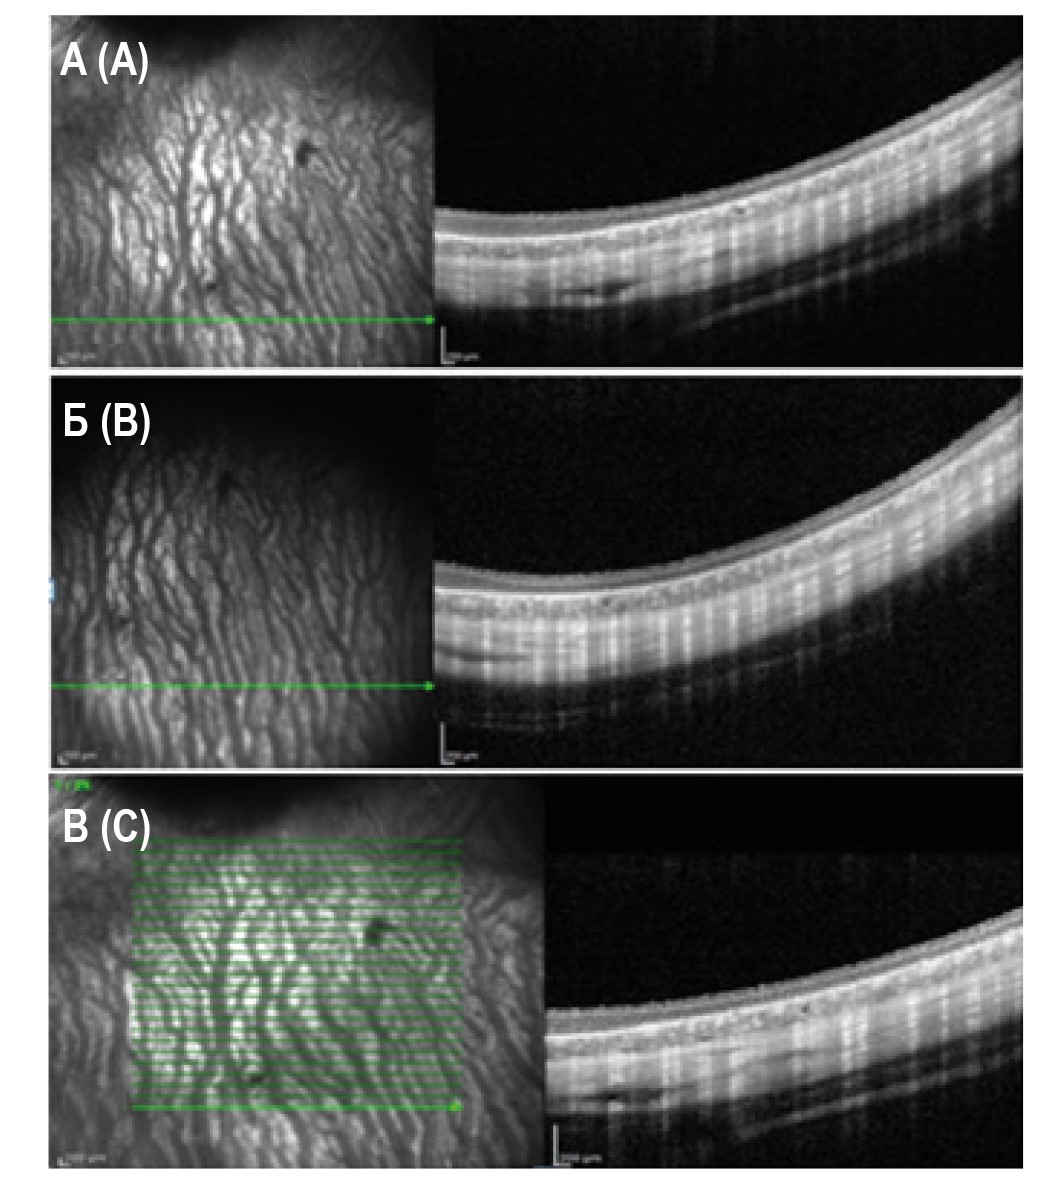

Во II группе с атрофией РПЭ до трансплантации, по данным ОКТ, обнаруживалась область повышенного проникновения сканирующего луча в подлежащие ткани, соответствующая области атрофии РПЭ (рис. 2А).

Рисунок 2. ОКТ-снимки, выполненные в сроки до и в разные сроки наблюдения при проведении субретинальной трансплантации ИПСК-РПЭ животным в глаз атрофией РПЭ (II группа), горизонтальный срез: А – до операции; Б – на 14-е сутки; В – на 28-е сутки и более

Примечание. Объяснение в тексте статьи.

Figure 2. OCT images performed at pre- and at different follow-up times during subretinal transplantation of IPSCs – RPE animals into the eye with RPE atrophy (group II), horizontal slice: A, preoperatively; B, on the 14th day; C, on 28 days and more

Note. Explanation in the text of the article.

На 14-е сутки после введения суспензии ИПСК-РПЭ в субретинальное пространство профиль сетчатки оставался сохранным, слои сетчатки дифференцировались, на срезах не выявлено ОКТ-признаков воспалительных и других патологических изменений сетчатки (рис. 2Б).

В позднем периоде наблюдения (28-60-е сутки) отмечается частичное уменьшение прохождения сканирующего луча под сетчатку, что может указывать на частичное восстановление клеток РПЭ. Осложнений и отрицательной динамики не было выявлено, слои сетчатки дифференцированы (рис. 2В).

Во время динамического контроля за животными на всех сроках наблюдения после оперативного вмешательства не было выявлено клинических и ОКТ-признаков воспаления и других патологических изменений сетчатки.